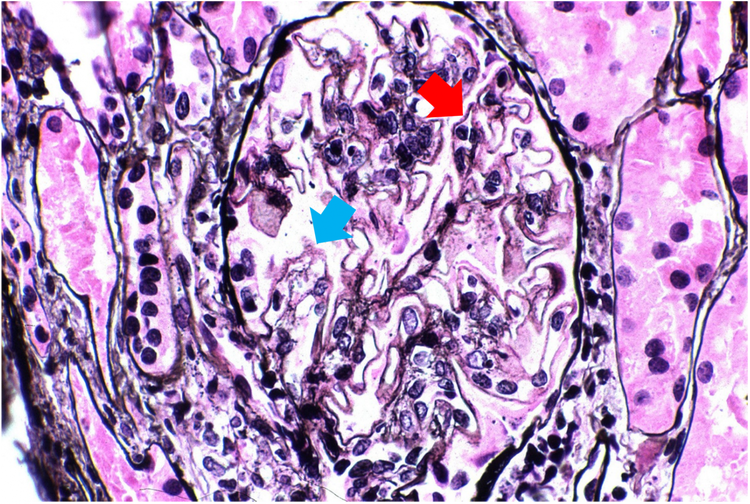

Mientras tanto, en la Figura 2, las muestras de pacientes en etapa avanzada de LN clase 5 muestran orificios difusos (flecha azul) y pequeños picos (flecha roja) a lo largo de las membranas basales glomerulares.3